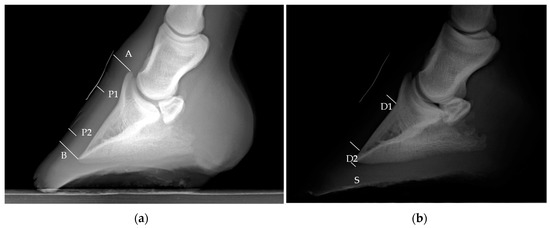

2.2. Measurements of the Hoof Internal Structures and Ultrasonographic Ratios

| Variables | DR | US | AN | n = 15 | |

|---|---|---|---|---|---|

| Median ± SD | Median ± SD | Median ± SD | p Value | ||

| Distance A | 14.1 ± 1.61 | 10.8 ± 1.51 | 13.67 ± 1.57 | 0.02 | - |

| Tubular hoof wall (P1) | 9.0 ± 1.15 | 6.6 ± 1.11 | 8.79 ± 1.13 | - | - |

| Parietal dermis (D1) | 7.1 ± 0.30 a | 8.1 ± 0.96 a | 5.7 ± 0.37 a | 0.19 | 0.01 |

| Lamellar layer (L1) | - | 5.8 ± 1.13 | 2.5 ± 0.68 | - | 0.01 |

| Sublamellar dermis (C1) | - | 2.25 ± 0.36 | 3.1 ± 0.52 | - | 0.01 |

| Tubular hoof wall (P2) | 8.7 ± 0.95 | 6.4 ± 0.64 | 8.58 ± 0.77 | - | - |

| Parietal dermis (D2) | 6.2 ± 0.62 a | 7.3 ± 0.60 a | 4.62 ± 0.67 a | 0.07 | 0.02 |

| Lamellar layer (L2) | - | 5.0 ± 0.97 | 2.3 ± 0.53 | - | 0.01 |

| Sublamellar dermis (C2) | - | 2.1 ± 0.48 b | 2.37 ± 0.46 b | - | 0.67 |

| Distance B | 15.2 ± 1.22 a | 13.8 ± 0.73 a | 14.1 ± 1.58 a | 0.07 | - |

| Sole dermis (S) | 6.0 ± 1.31 a | 4.9 ± 1.32 a | 6.17 ± 0.65 a | 0.12 | - |

| US ratios | Proximal | Distal | |||

| Mean ± SD | Mean ± SD | ||||

| D: A | 0.70 ± 0.03 | 0.66 ± 0.03 | |||

| L: D | 0.71 ± 0.02 | 0.68 ± 0.02 | |||

| C: D | 0.28 ± 0.01 | 0.30 ± 0.02 | |||

| Mean ± SD | |||||

| B: A | 0.84 ± 0.05 | ||||

| S: A | 0.44 ± 0.02 | ||||